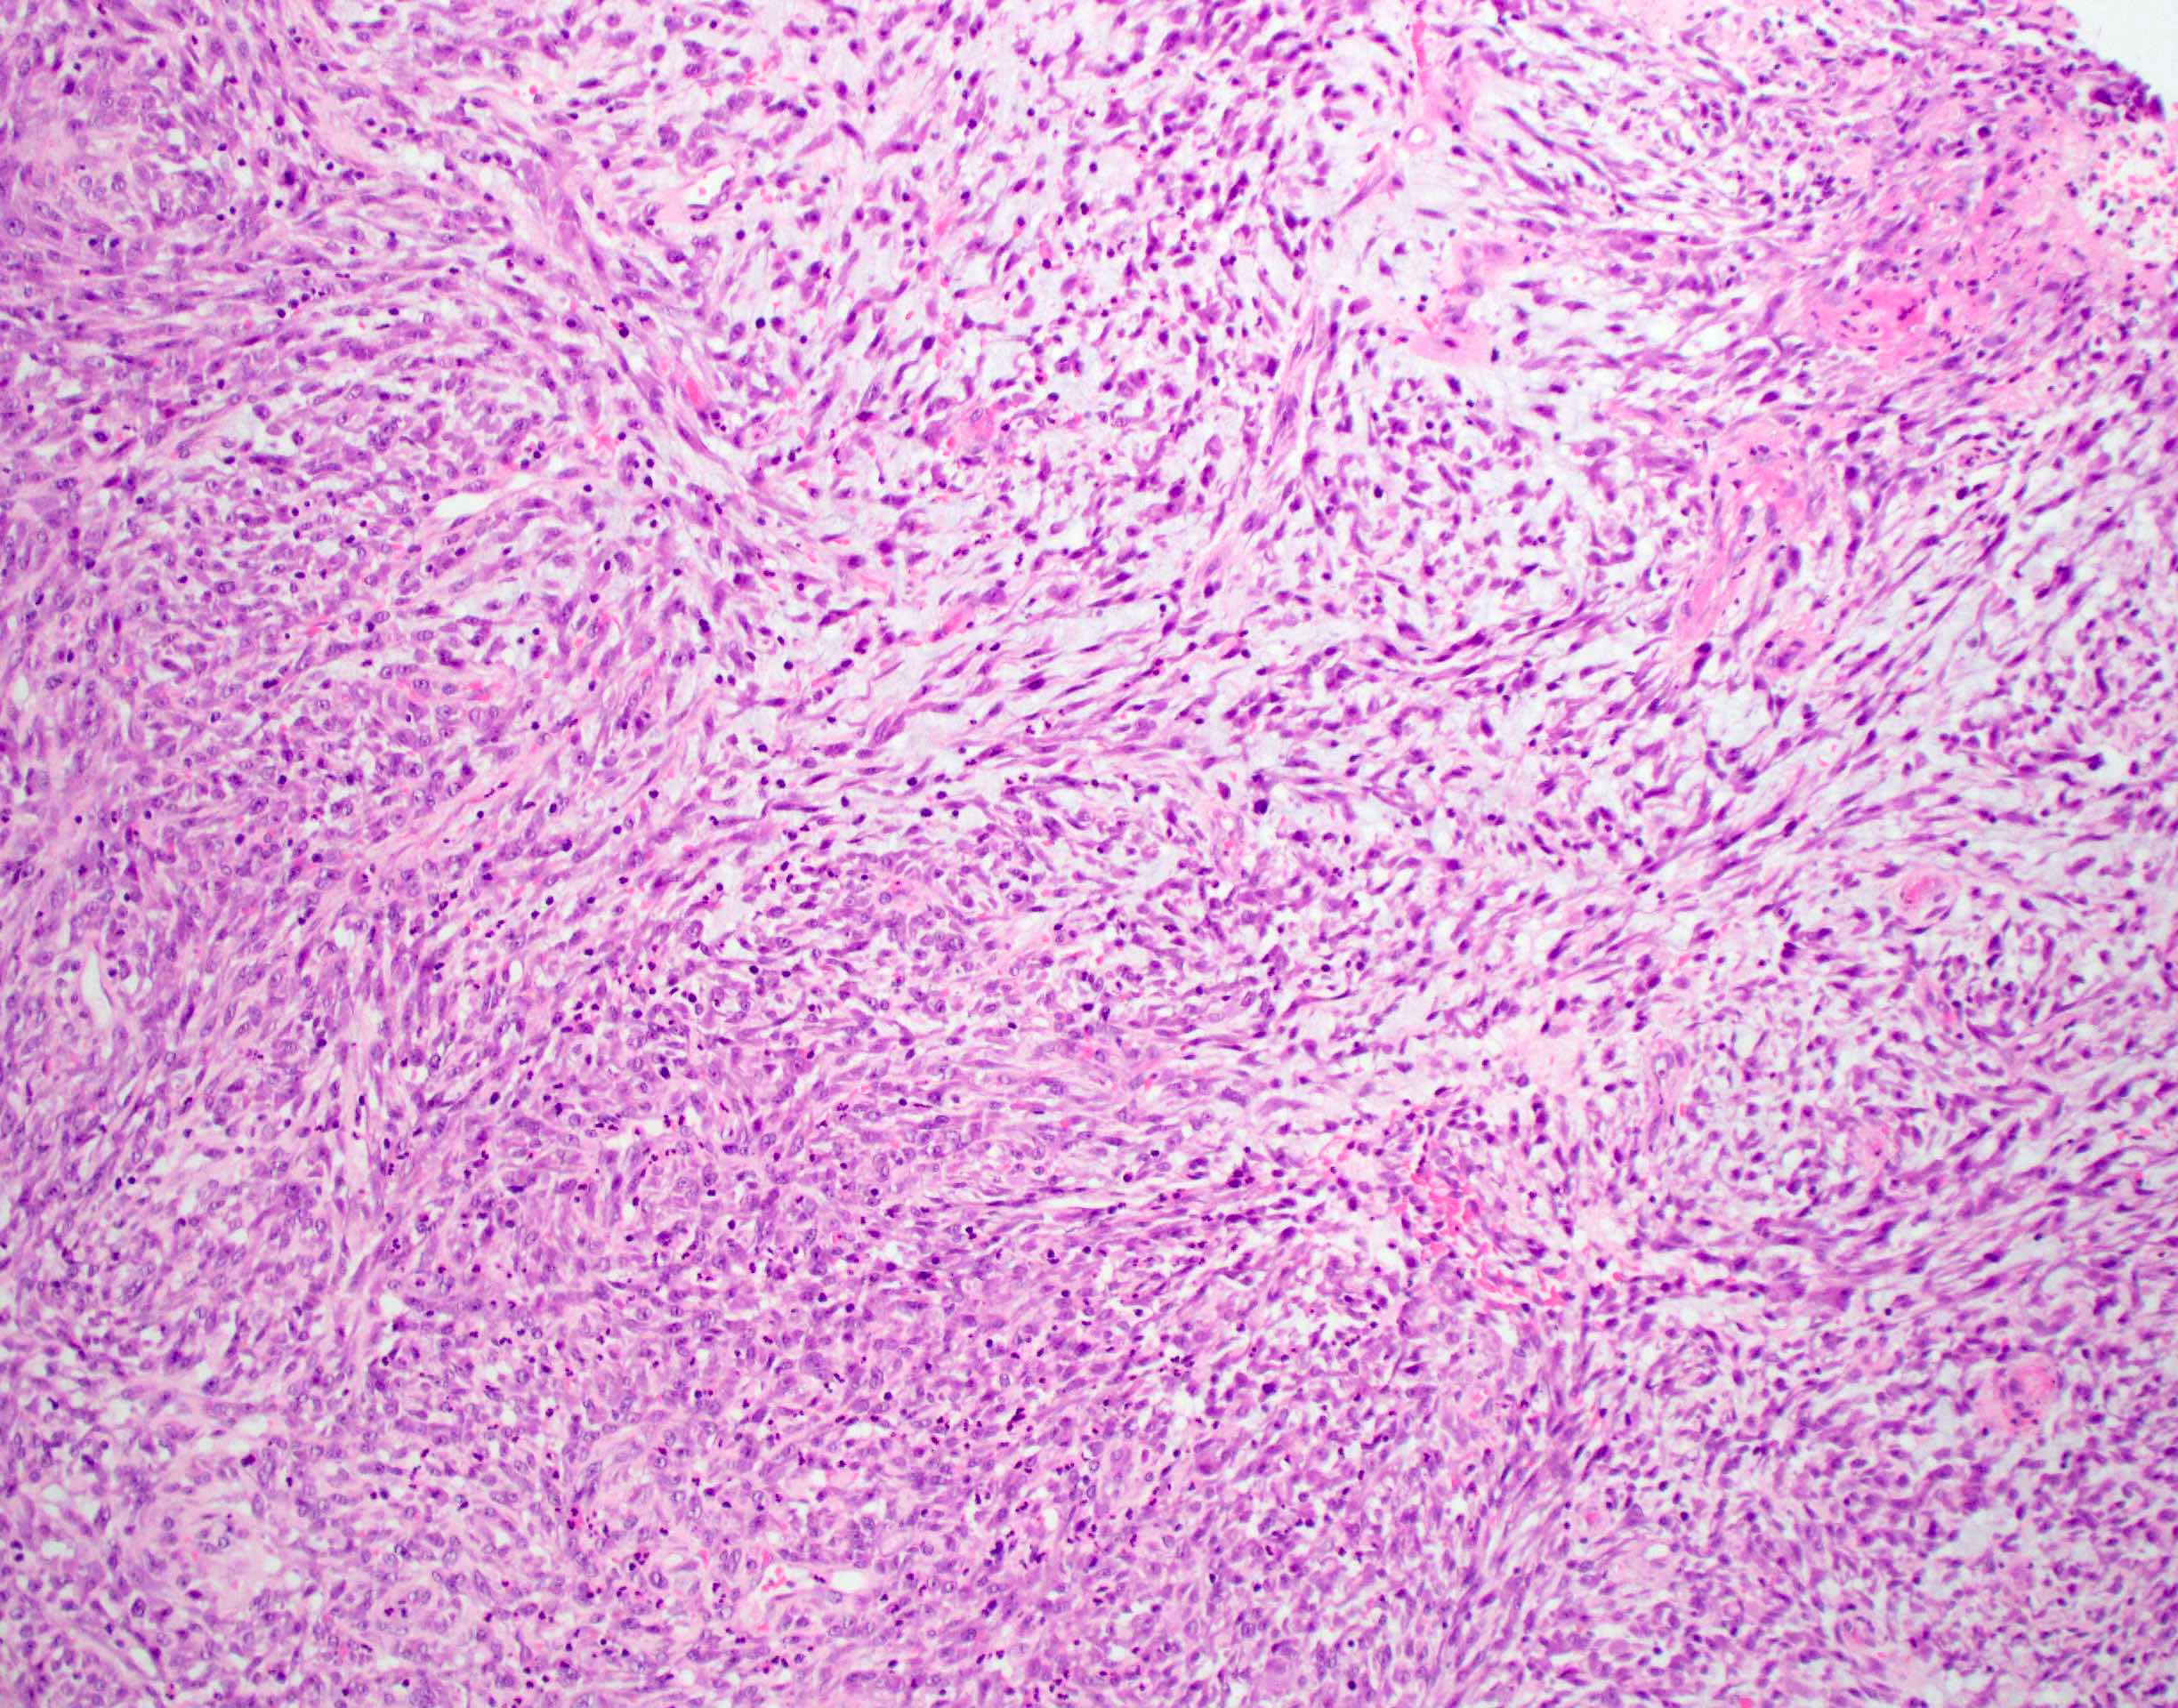

- Spindle cell / sarcomatoid squamous cell carcinoma (Am J Otolaryngol 2008;29:123)

- Most commonly occurs postradiotherapy or as second primary

- Mesenchymal in appearance

- Atypical plump spindled cells arranged in fascicles or storiform pattern

- May have metaplastic or neoplastic cartilage or bone

Microscopic (histologic) images

Contributed by Ruta Gupta, M.B.B.S., M.D.